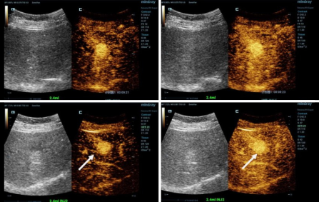

Ультразвуковая диагностика